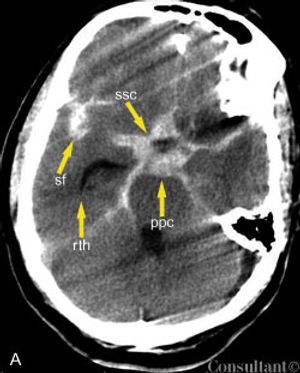

A 69-year-old man with an acute severe headache and nausea was brought to the emergency department. The patient was neurologically intact; an intracerebral hemorrhage was suspected.